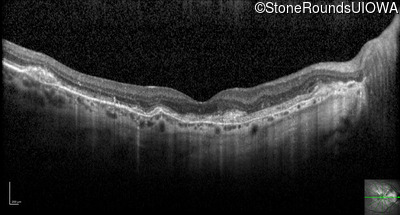

Optical Coherence Tomography - Right - 20/25 +1

Exemplar / OCT Stack